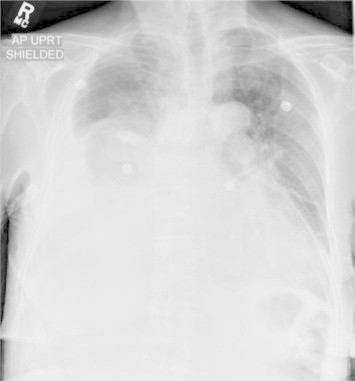

Her chest radiographs (Figs. 1 and 2) demonstrated a large right pleural effusion with associated atelectasis. Underlying pneumonia could not be excluded. There was also a small left pleural effusion.

Fig. 1.

Lateral chest radiograph at the time of admission.

Fig. 2.

Anteroposterior (AP) chest radiograph at the time of admission.